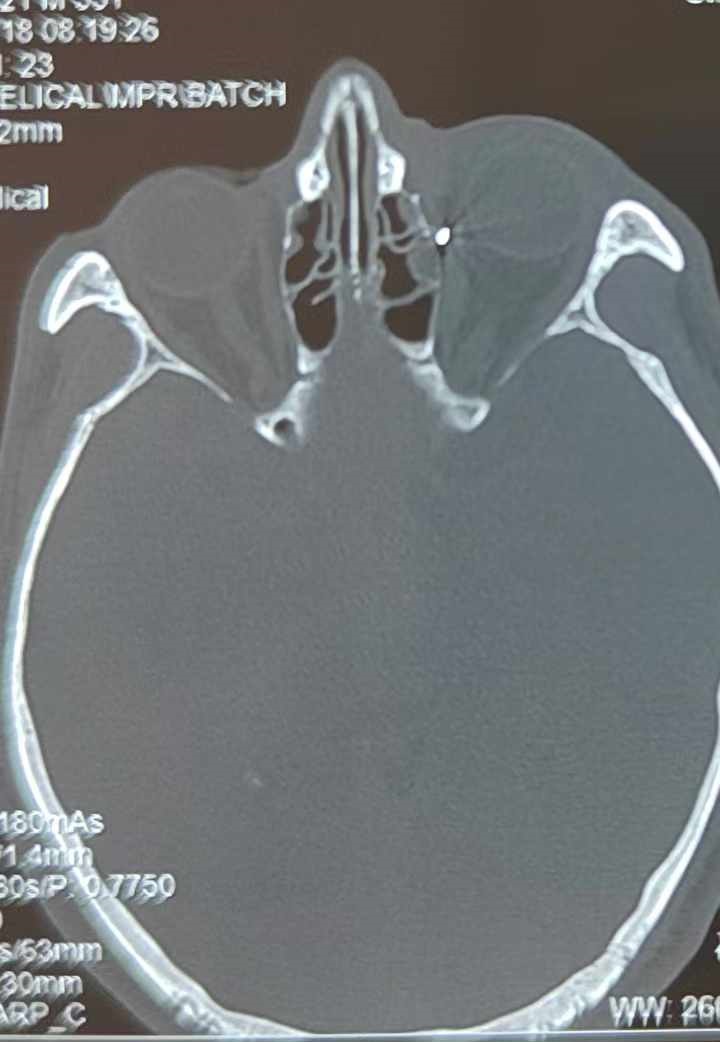

從CT報(bào)告中可以看出,高先生眼內(nèi)的異物不是很大,但位于眼窩深處,緊鄰鼻骨,從CT影像判斷應(yīng)該是金屬或合金異物。一般臨床上遇到這樣的情況,醫(yī)生會(huì)建議“保守觀察”,若異物傷及神經(jīng)、發(fā)生炎癥感染等,則需到條件較好、有眼眶病和眼外傷專業(yè)醫(yī)師的醫(yī)院進(jìn)行二期眶內(nèi)異物取出術(shù)(2021年《中國(guó)眼眶異物診斷和治療專家共識(shí)》)。

李海波博士介紹,眶內(nèi)異物想要通過手術(shù)取出,難度很大,一是因?yàn)槲恢秒[匿,無法實(shí)現(xiàn)可視化操作;二是如果是磁性異物,現(xiàn)有手術(shù)工具磁性強(qiáng)度有限,很難吸出這么深的異物;三是可操作空間極為狹小,眶周軟組織多,異物周邊包裹緊密,像高先生這種情況,異物周邊還有很多神經(jīng)、血管,手術(shù)難度更高。